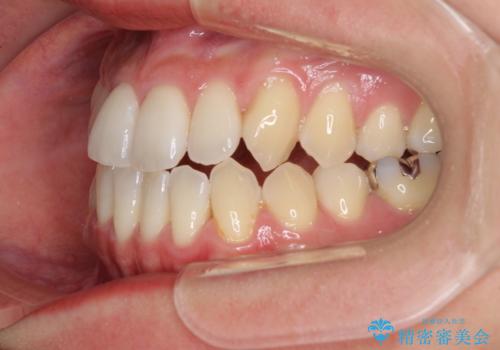

前歯のデコボコ インビザラインによる矯正治療

- 上下前歯の叢生と奥歯の反対咬合を気にして来院された患者様です。

インビザラインを用い、下顎はIPR(歯と歯の間を削る)と歯列全体を後方に移動させ、上顎は側方に拡大させることで歯列を改善していくこととしました。

骨格的に下顎が左側前方にずれているため、上下正中のズレや左右奥歯の咬み合わせを理想的な状態とすることは困難でした。